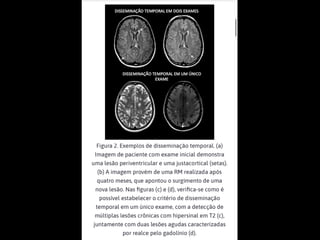

critérios  McDonald  (2017)   • disseminação  no  espaço   – RM  por  ≥  1  lesões  hiperintensas  em  T2,   sintomá+cas  ou  assintomá+cas,  que  são   caracterís+cos  de  EM,  em  dois  ou  mais  das   seguintes  quatro  áreas  do  sistema  nervoso   central:     • periventricular,     • cor+cal/justacor+cal,  infratentorial  e  medula  espinhal.

• 45.

• disseminação  no  tempo   – presença  simultânea  de  lesões  captantes  de   gadolíneo  e  lesões  não  captantes  em  qualquer   exame  de  RM,     – ou  nova  lesão  hiperintensa  em  T2  ou  captante  de   gadolínio  quanto  comparada  a  um  exame  de  RM   prévio,  independentemente  do  momento  em  que   foi  realizado.